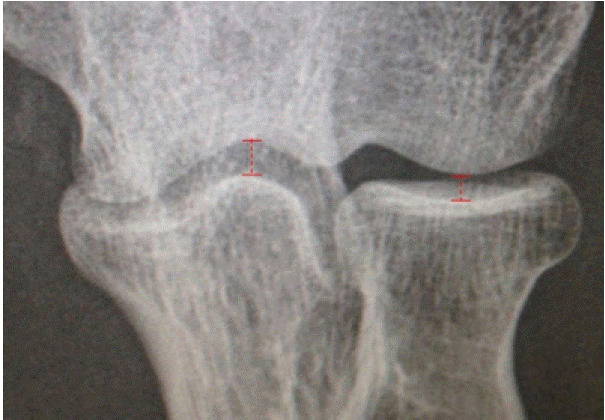

Methods: Indications and the surgical technique of the AMOR procedure are described. A retrospective observational service evaluation study was conducted from electronic patient records. Collected clinical outcomes included range of motion, pain level, subjective functional score, and general satisfaction with the results of the procedure. The radiographic outcome was radiocapitellar joint space.

Results: Between 2017 and 2021, eight consecutive patients underwent AMOR as part of an arthroscopic osteocapsular arthroplasty procedure. Radiographically, the mean radiocapitellar joint space improved from an average of 1.7 mm to 4.6 mm. Clinically, the mean pain score decreased from 8/10 to 3/10. Six of the eight patients (75%) were satisfied with their results. In two cases, initial improvement following surgery lasted less than 1 year, and one of these patients underwent total elbow arthroplasty for painful ulnohumeral osteoarthritis. There were no complications of surgery recorded.